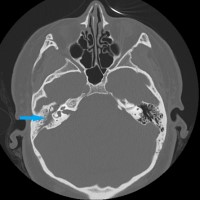

Intraoperative photo demonstrating the operative approach. A right temporal craniotomy has been made and the covering of the brain, the dura mater, is being dissected off of the base of the skull. Orientation: this is the right side of the head; the ear is just off the top of the frame (green star(*)), the nose is to the left, the back of the head the right, and the top of the head is toward the bottom.

Intraoperative video demonstrating the dissection of the encephalocele. Note the band of tissue extending from the skull base defect on the top of the image through the dural defect toward the bottom. This is the encephalocele.